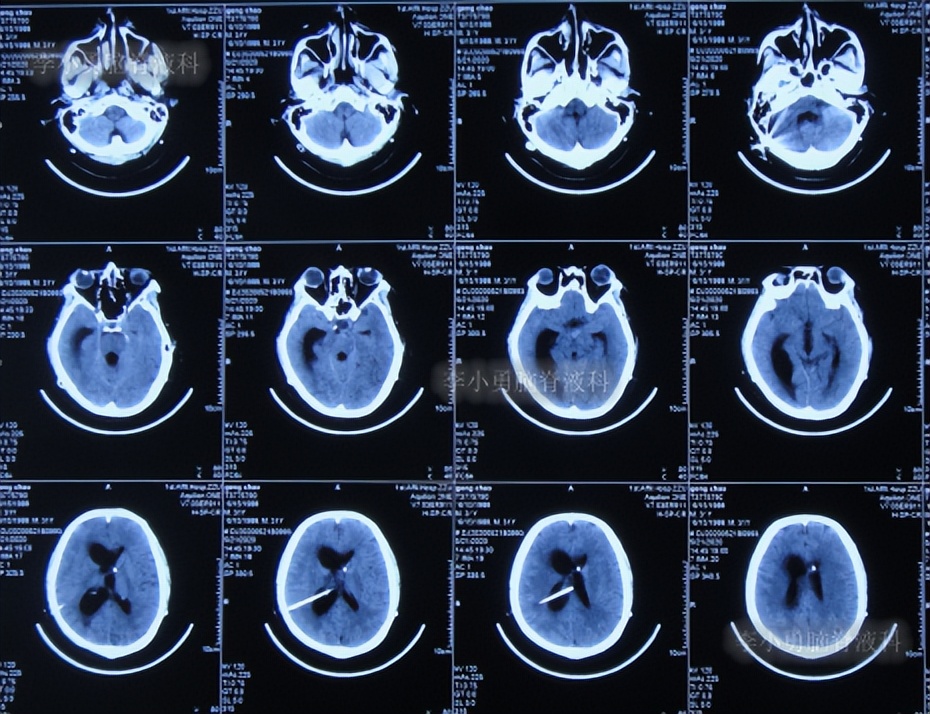

入院后2天即2020年6月6日,进行了脑室腹腔分流管拔除术+脑室穿刺外引流术(图-21)。

图-21:2020年6月6日头颅CT

2020年6月8日(住院治疗4天),查头颅CT示脑室有所缩小,有少量积血(图-22),引流管培养出表皮葡萄球菌感染。

图-22:2020年6月8日头颅CT

2020年6月10日(住院治疗6天),查头颅CT示脑室缩小(图-23)。

图-23:2020年6月10日头颅CT

2020年6月22日(住院治疗18天),进行了双侧脑室腹壁外引流术(图-25)。

图-25:2020年6月22日头颅CT

2020年7月3日(入院治疗29天),查头颅CT示双侧脑室缩小,但第四脑室稍有增大(图-27)。

图-27:2020年7月3日头颅CT

2020年7月27日(住院治疗53天),查头颅CT示第四脑室进一步扩张(图-28),继续观察。

图-28:2020年7月27日头颅CT

2020年7月28日(住院治疗54天),因第四脑室扩张意识变差,进行了第四脑室腹壁外引流术,术前术后头颅CT对比(图-29)。

图-29:2020年7月28日术前术后头颅CT

2020年9月14日(住院治疗102天),拔除了一侧脑室引流管(图-31)。

图-31:2020年9月14日头颅CT

于2020年10月21日(住院治疗139天),进行了侧脑室和四脑室腹腔分流术。

于2020年10月30日(住院治疗148天),查头颅CT示脑室未见异常(图-32)。

图-32:2020年10月30日头颅CT

2020年11月3日(住院治疗152天)出院,出院时:意识变清,自己站立变稳,能自己走路,双眼对视有好转(图-33)。

图-33:2020年11月3日出院时